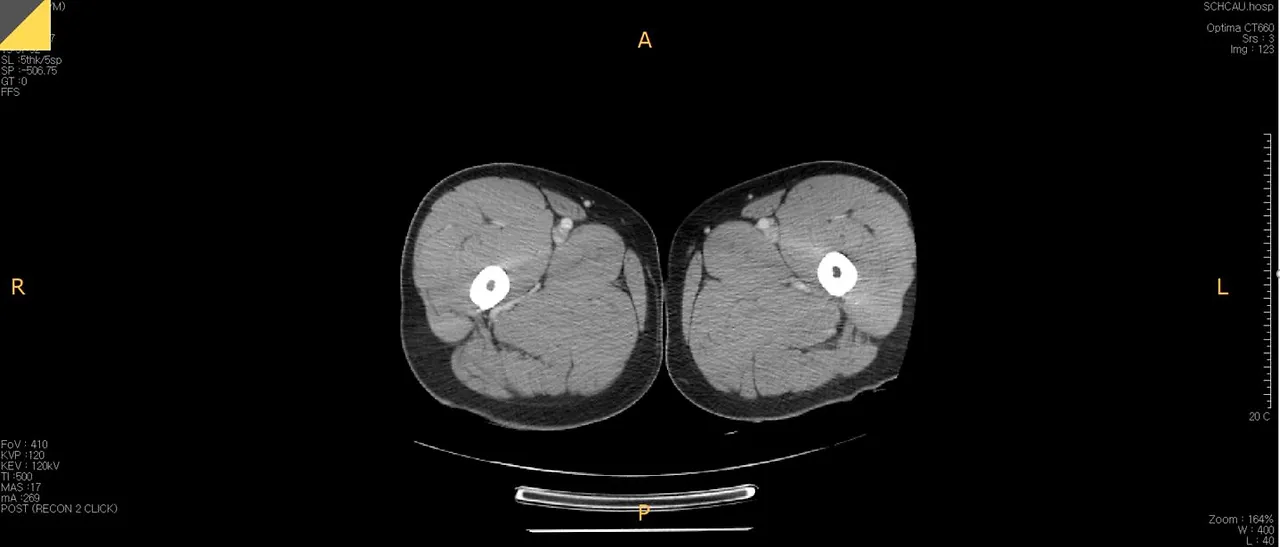

허벅지CT.JPG

참고로 이건 제 허벅지 사진입니다. 여기에는 표시하지 않았지만 제 허벅지 한쪽의 지름은 약 22cm 정도 되고 보시면 근육이 대부분이고 살이 별로 없는 것처럼 보입니다. 그래서 ‘나는 피하지방은 괜찮아~’라고 생각했는데 이번에 찍은 CT에서는 그게 아닌 것이 밝혀졌습니다. (허리살이요ㅠㅠ)